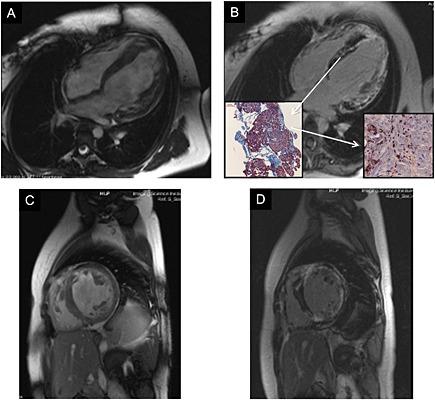

We report the case of a 17-year-old female patient with known hypertrophic cardiomyopathy and a Wolff-Parkinson-White syndrome. She came to our department for further evaluation of a new diagnosed dilated cardiomyopathy characterized by an enlargement of the left ventricle and a fall in ejection fraction. Clinically, she complained about atypical chest pain, arrhythmic episodes with presyncopal events, and dyspnea (NYHA III) during the last 6 months. Non-invasive and invasive examinations including magnetic resonance imaging, electrophysiological examinations, and angiography did not lead to a conclusive diagnosis. Therefore, endomyocardial biopsies (EMBs) were taken to investigate whether a specific myocardial disease caused the impairment of the left ventricular function. EMB analysis resulted in the diagnosis of a virus-negative, active myocarditis. Based on this diagnosis, an immunosuppressive treatment with prednisolone and azathioprine was started, which led to an improvement of cardiac function and symptoms within 3 months after initiating therapy. In conclusion, we show that external stress triggered by myocarditis can induce a reversible transition from a hypertrophic cardiomyopathy to a dilated cardiomyopathy phenotype. This case strongly underlines the need for a thorough and invasive examination of heart failure of unknown causes, including EMB investigations as recommend by the actual ESC position statement.

我们报告了一例17岁女性患者,她患有肥厚型心肌病和预激综合征。她因新诊断的扩张型心肌病前来我院进一步评估,其特征为左心室扩大和射血分数下降。临床上,她在过去6个月中出现非典型胸痛、伴有晕厥前期事件的心律失常发作以及呼吸困难(纽约心脏协会III级)。包括磁共振成像、电生理检查和血管造影在内的非侵入性和侵入性检查均未得出明确诊断。因此,进行了心内膜心肌活检(EMB),以调查是否存在特定的心肌疾病导致左心室功能受损。EMB分析诊断为病毒阴性的活动性心肌炎。基于这一诊断,开始使用泼尼松龙和硫唑嘌呤进行免疫抑制治疗,治疗开始后3个月内心脏功能和症状得到改善。总之,我们表明心肌炎引发的外部应激可诱导从肥厚型心肌病到扩张型心肌病表型的可逆转变。该病例强烈强调了对病因不明的心力衰竭进行全面和侵入性检查的必要性,包括按照欧洲心脏病学会(ESC)现行立场声明的建议进行EMB检查。